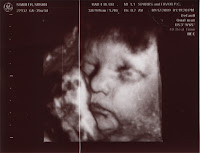

Well, we had our last ultrasound today. Everything looks PERFECT. Baby Stabler is head down and ready to make its debut here in a few weeks. The ultrasound was amazing, it looks just like a little baby in there! We got to see it open and close its eyes and smile and what looked like grunting. Haha! I think it looks alot like Stan but I still don't know if I think its a boy or a girl.

See pictures and video below!